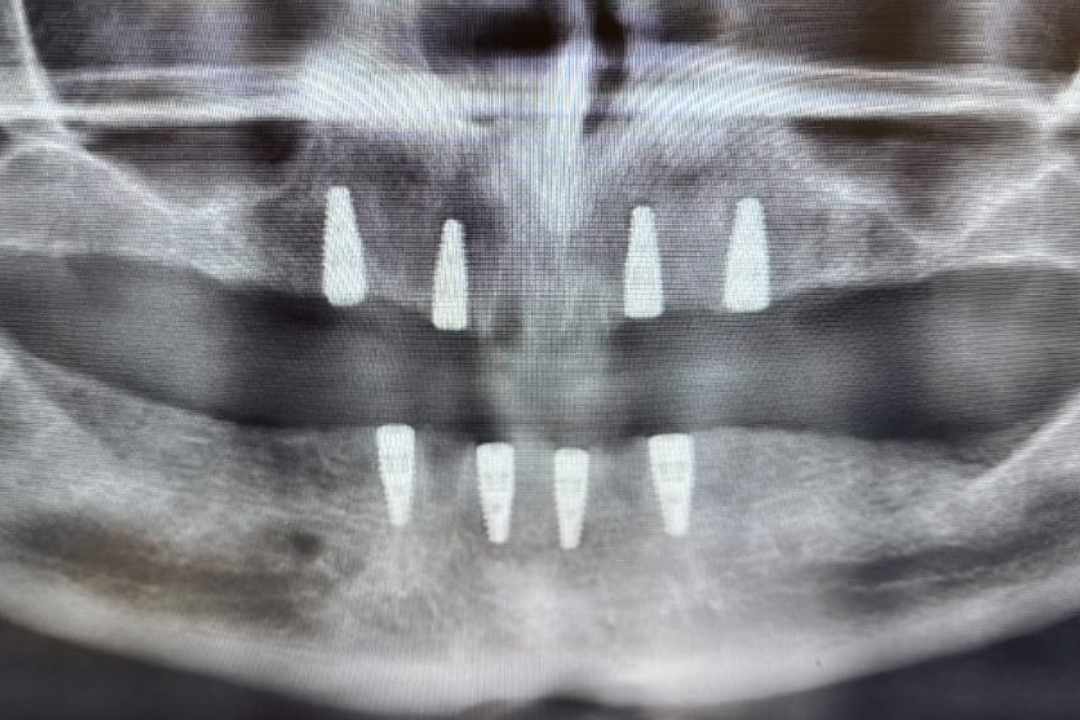

Dental implants are the most advanced solution for replacing missing teeth. These small, biocompatible titanium posts act as artificial tooth roots that are surgically placed into the jawbone. Over a few months, the implant fuses directly with the bone, creating an incredibly strong and stable base for a custom-made crown.

All-on-4® Full Mouth Dental Implants: A revolutionary technique that can replace an entire arch of failing or missing teeth with a stable, permanent set of new teeth, often in a single procedure. This is the ultimate alternative to traditional dentures.